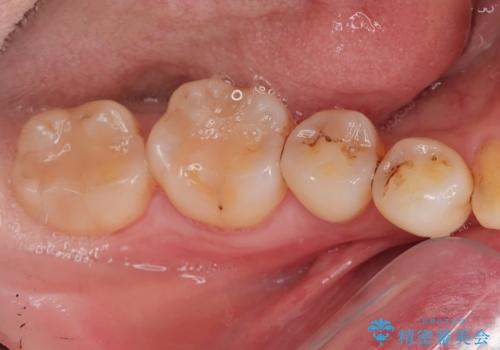

親知らず抜きたい。

- 親知らずを抜歯したいとの事で来院。

パノラマ,CT撮影を行い安全なことを確認して抜歯を行いました。